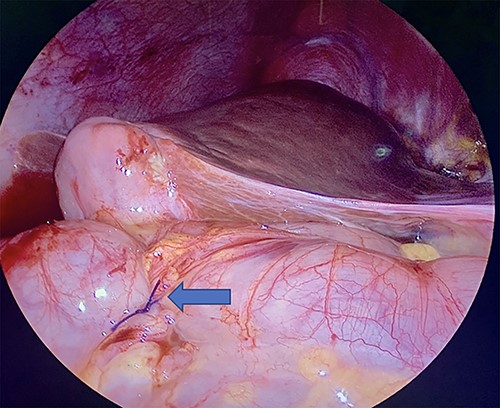

Diagnostic laparoscopy of the abdomen was performed demonstrating diffuse carcinomatosis secondary to known primary gallbladder carcinoma. A portion of the ascending colon was adherent to the abdominal wall and was carefully dissected off. There was no full thickness erosion of the stent, and the stent was palpated through the colon at the ascending colon using bowel graspers. Colonoscopy was next performed, identifying the stent lodged in the mid-ascending colon and another intraluminal portion of the proximal transverse colon that appeared abnormal (Fig. 2A and B). The stent was successfully removed with rat tooth forceps by gastroenterology. The colorectal surgery team then performed two serosal suture repairs on the ascending and transverse colon (Fig. 3).

(A) Ascending colon demonstrating ulceration and the biliary stent lodged within colonic wall. (B) Stent across transverse colon with punctate erythema.

Laparoscopic visualization of a serosal lembert suture placement on transverse colon (as indicated by arrow; ascending colon serosal repair not featured).